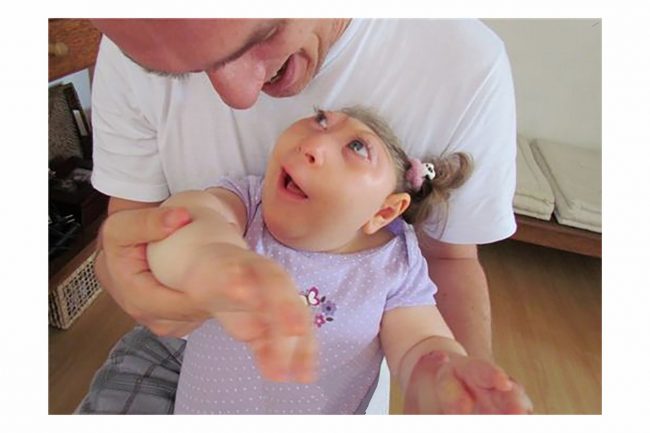

Oggi sappiamo che la sindrome alcolico fetale si traduce in:

dismorfologie facciali e i problemi cerebrali

deficit di crescita

alterato sviluppo del cranio

Lo strumento che si vuole utilizzare è quello di un incontro/dibattito sul tema con gli studenti delle classi di quinta superiore e la distribuzione di un opuscolo, alle sole studentesse, contenente informazioni, consigli e alcune immagini shock (così come quelle utilizzate dal Ministero della Sanità per la campagna contro l’uso di sigarette) per attirare l’attenzione e far riflettere.